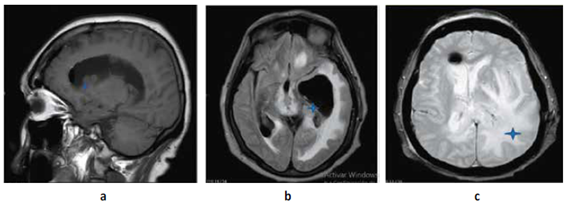

Paciente mujer de 73 años natural de Lima Perú con tiempo de enfermedad de 2 meses caracterizado por trastorno del sensorio, vómitos, cefalea y alteración de marcha; al examen físico neurológico se evidencia desorientación, hemiparesia derecha a 2/5 (Escala de Daniels), Babinsky derecho (+) Hoffmann derecho (+), parálisis facial central izquierda. motivo por el cual se realiza resonancia magnética cerebral (RMN) con contraste (c/c) evidenciando lesiones de aspecto nodular que comprometen ventrículos laterales, con extensión al III Y IV ventrículo, condicionando edema perilesional e hidrocefalia con signos de efecto hipertensivo Figura N°1; Se decide manejo quirúrgico de emergencia colocación de un sistema de derivación ventrículo peritoneal bilateral Figura N°2 y N°3. Ya con el paso de los días y mejoría del cuadro de hipertensión endocraneana resuelto se decide realizar biopsia guiada por estereotaxia obteniéndose por resultado de anatomía patológica proceso linfoproliferativo de células redondas atípicas correspondientes a células B maduras. Motivo por el cual se decide tratamiento oncológico con uso de radioterapia (10 sesiones) y corticoides que se realiza durante 3 meses; Es dada de alta con mejoría clínica. Al cabo de 4 meses el paciente acude para su control, se realiza tomografía cerebral (TEM) sin contraste (SC)Figura N°3evidenciando ausencia casi total de la tumoración y mejoría de los síntomas.